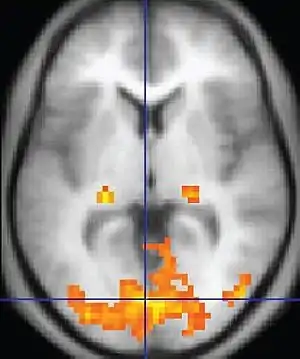

Et fMRI-billede med gule områder der viser den øgede aktivitet i forhold til en kontrol.